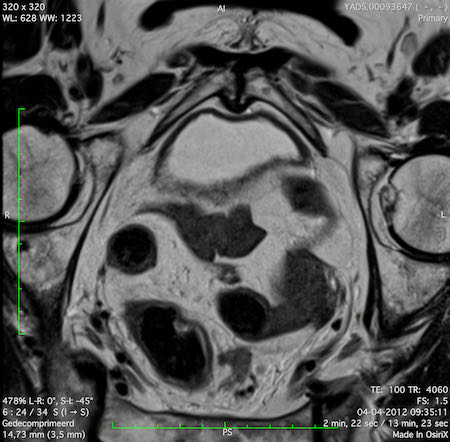

Hình ảnh

Các hình ảnh được cung cấp cho thấy ung thư biểu mô tế bào nhẫn với tình trạng dày lan tỏa thành trực tràng, hình ảnh bia bắn điển hình, và sự xâm lấn mỡ mạc treo trực tràng.